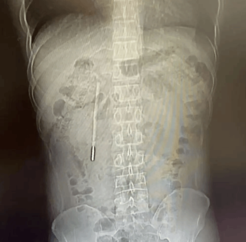

【单机】体内待了20年!男子12岁时误吞水银体温计 32岁因腹痛才取出

据“温医大附一院内镜中心”官方发布,近日,浙江温州32岁的王先生因腹部不适就医。